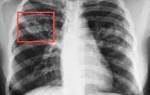

Туберкулез может поражать различные органы и ткани человека (12 — 17%): глаза, кости, кожу, мочеполовую систему, кишечник и т.д. Тогда туберкулез называется внелегочным, но чаще всего встречается туберкулез легких (83 — 88 %). Цирротический туберкулез легкого Милиарный туберкулез Что происходит

Что происходит? Палочка Коха попадает в человеческий организм и приводит к изменению состояния иммунной системы. При активной форме туберкулеза палочка Коха быстро размножается в легких больного и питается человеческими тканями, разрушая легкие, отравляя организм человека продуктами своей жизнедеятельности. Вместе с кровью и лимфой она может распространяться по всему организму.